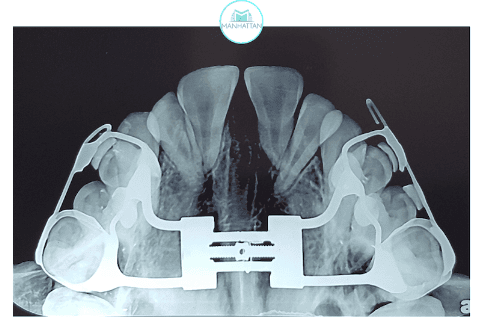

O primeiro objetivo foi corrigir a mordida cruzada e estimular o crescimento da parte superior do rosto (maxila), trazendo equilíbrio entre as arcadas.

Expansão da maxila: Utilizamos um aparelho especial chamado disjuntor, adaptado para esse caso. Ele foi ativado diariamente, abrindo espaço na arcada superior. Em apenas 15 dias, já foi possível corrigir a mordida cruzada posterior.